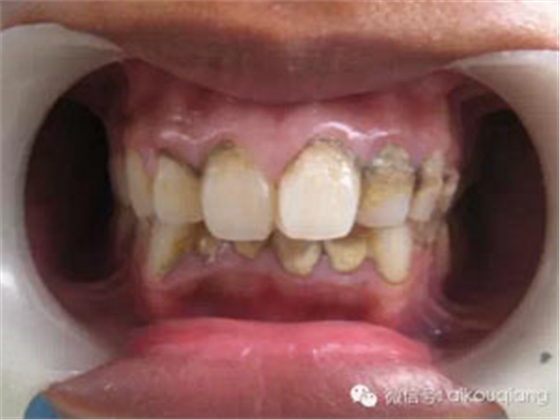

一個(gè)高職學(xué)校的學(xué)生,口腔內(nèi)嚴(yán)重的牙結(jié)石,可能小時(shí)候沒(méi)有刷過(guò)牙

洗牙(潔治)后效果很明顯